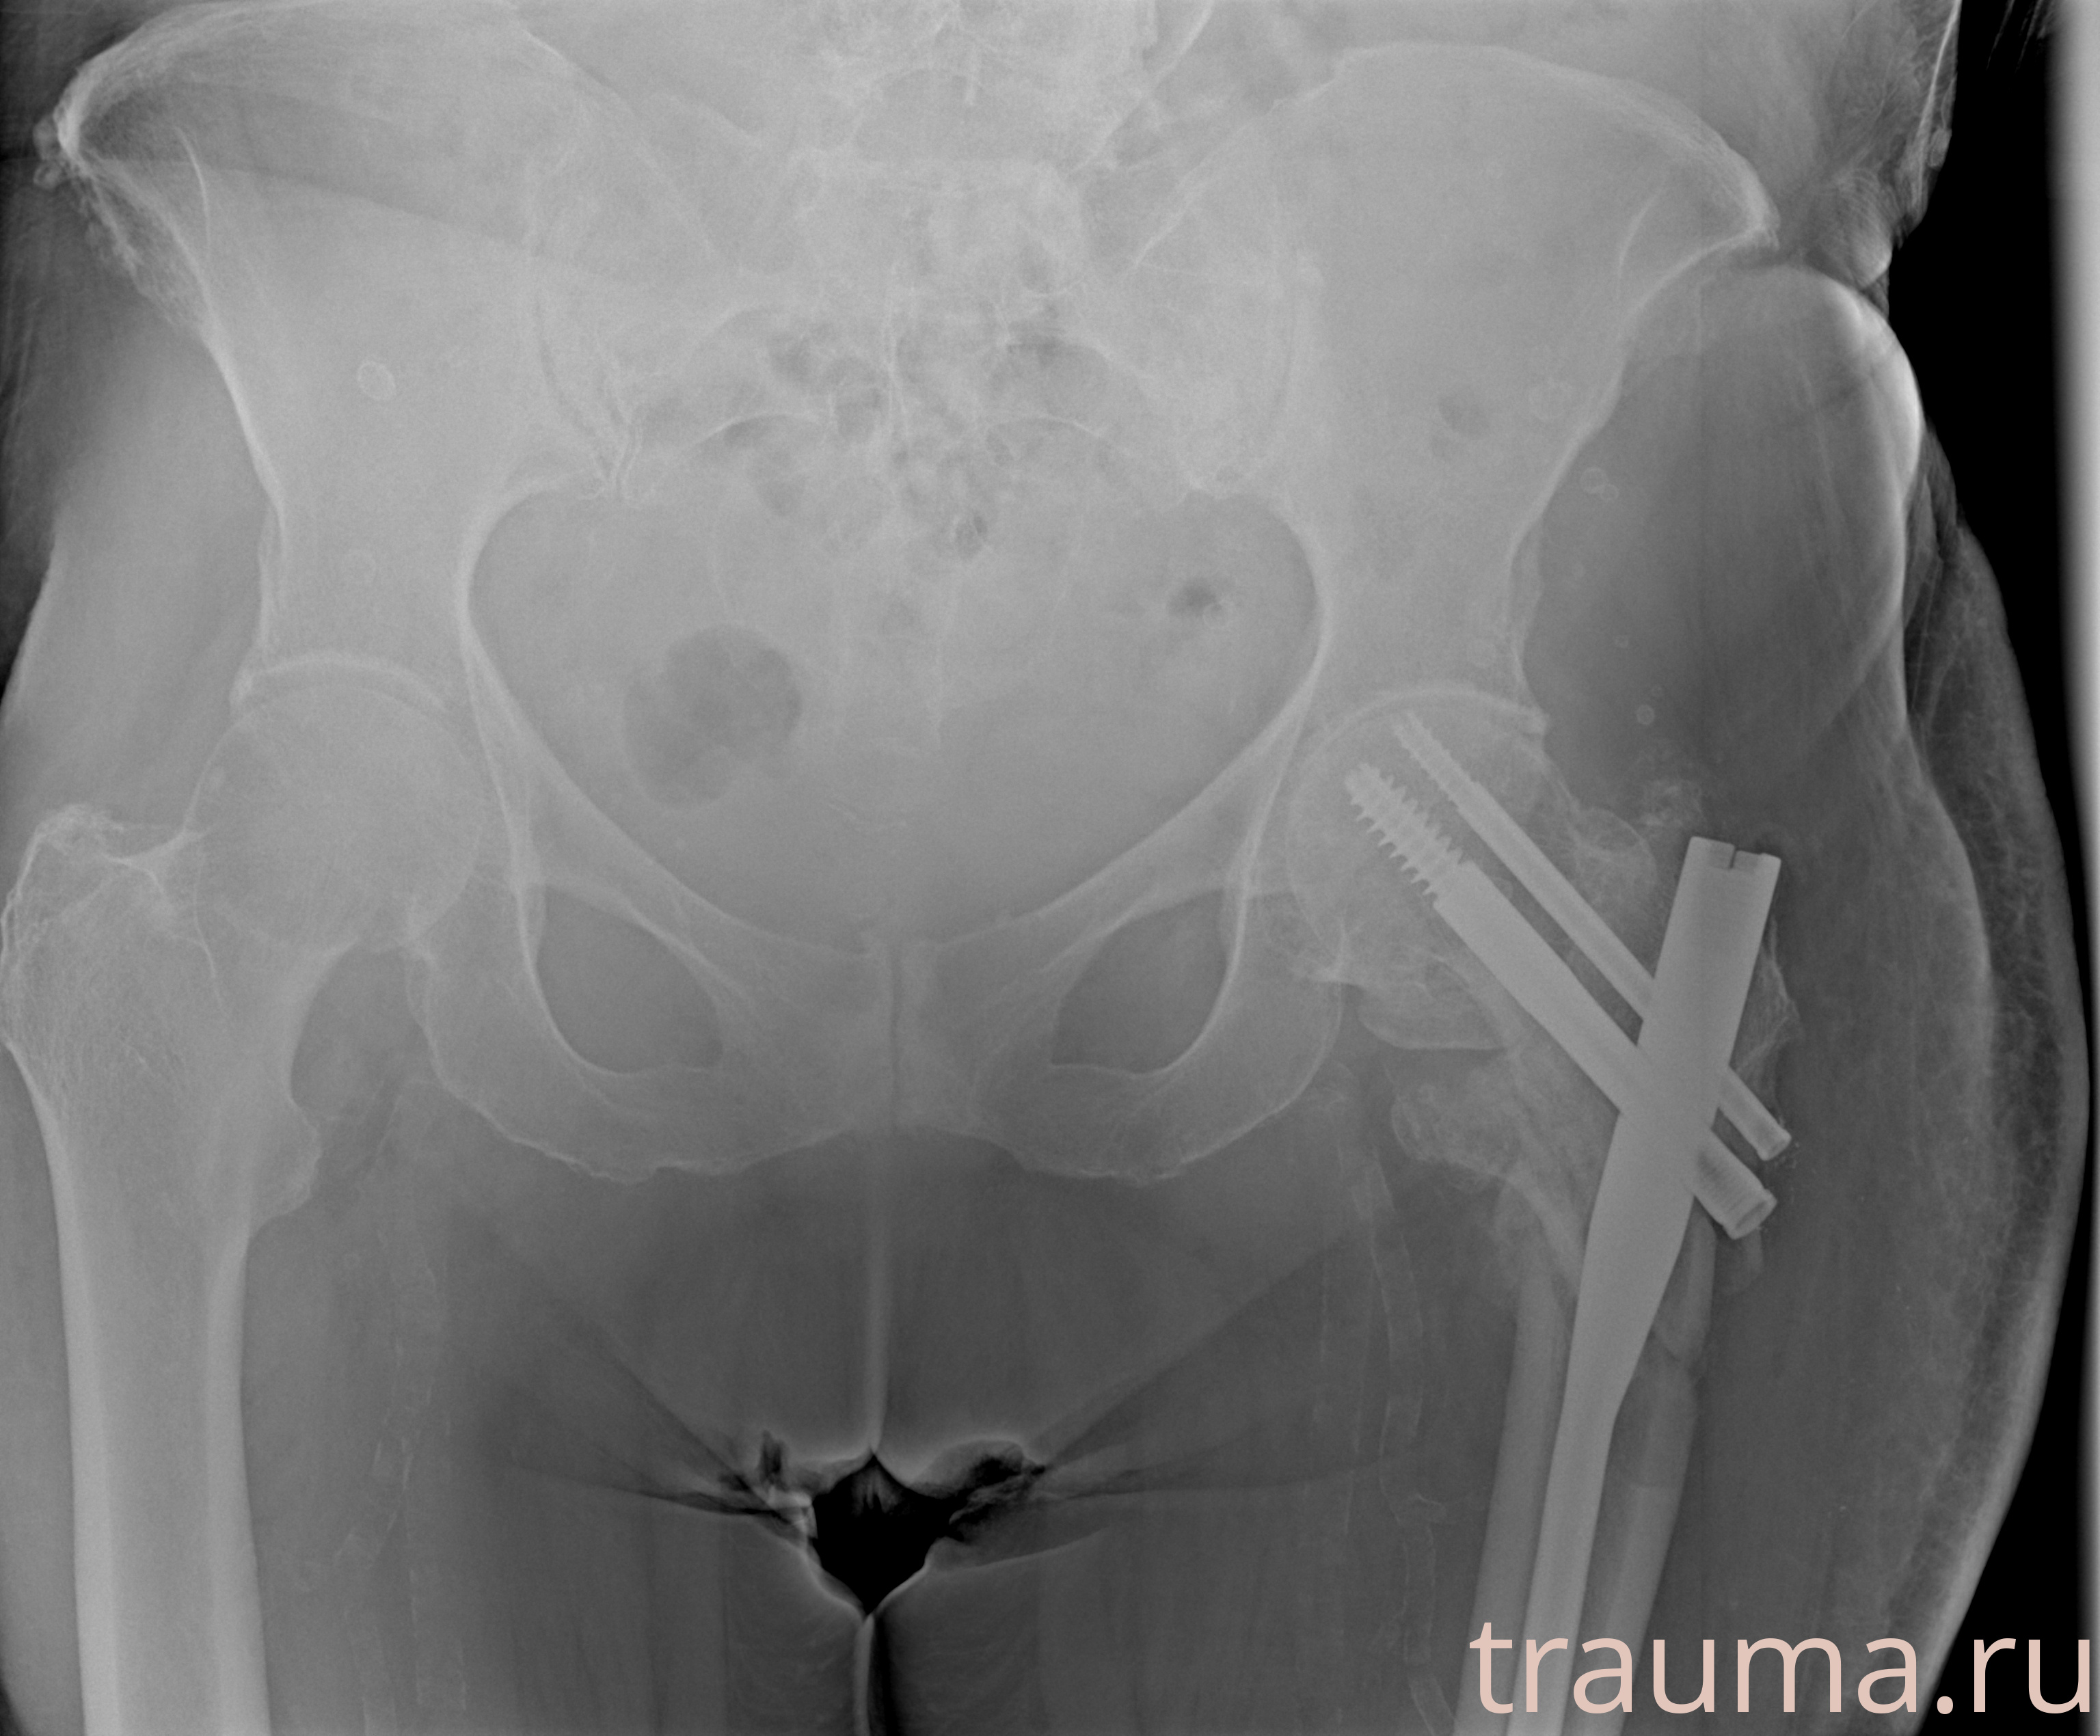

Рентгенограммы

Рентген на дому: по вашему адресу приезжает врач-рентгенолог, травматолог-ортопед с мобильным рентгеновским аппаратом, проводит диагностику травмы или заболевания, делает необходимые рентгенограммы, дает рекомендации по дальнейшему лечению. Получить качественные снимки в домашних условиях возможно благодаря уникальной методике, разработанной МосРентген Центром для института  Склифосовского